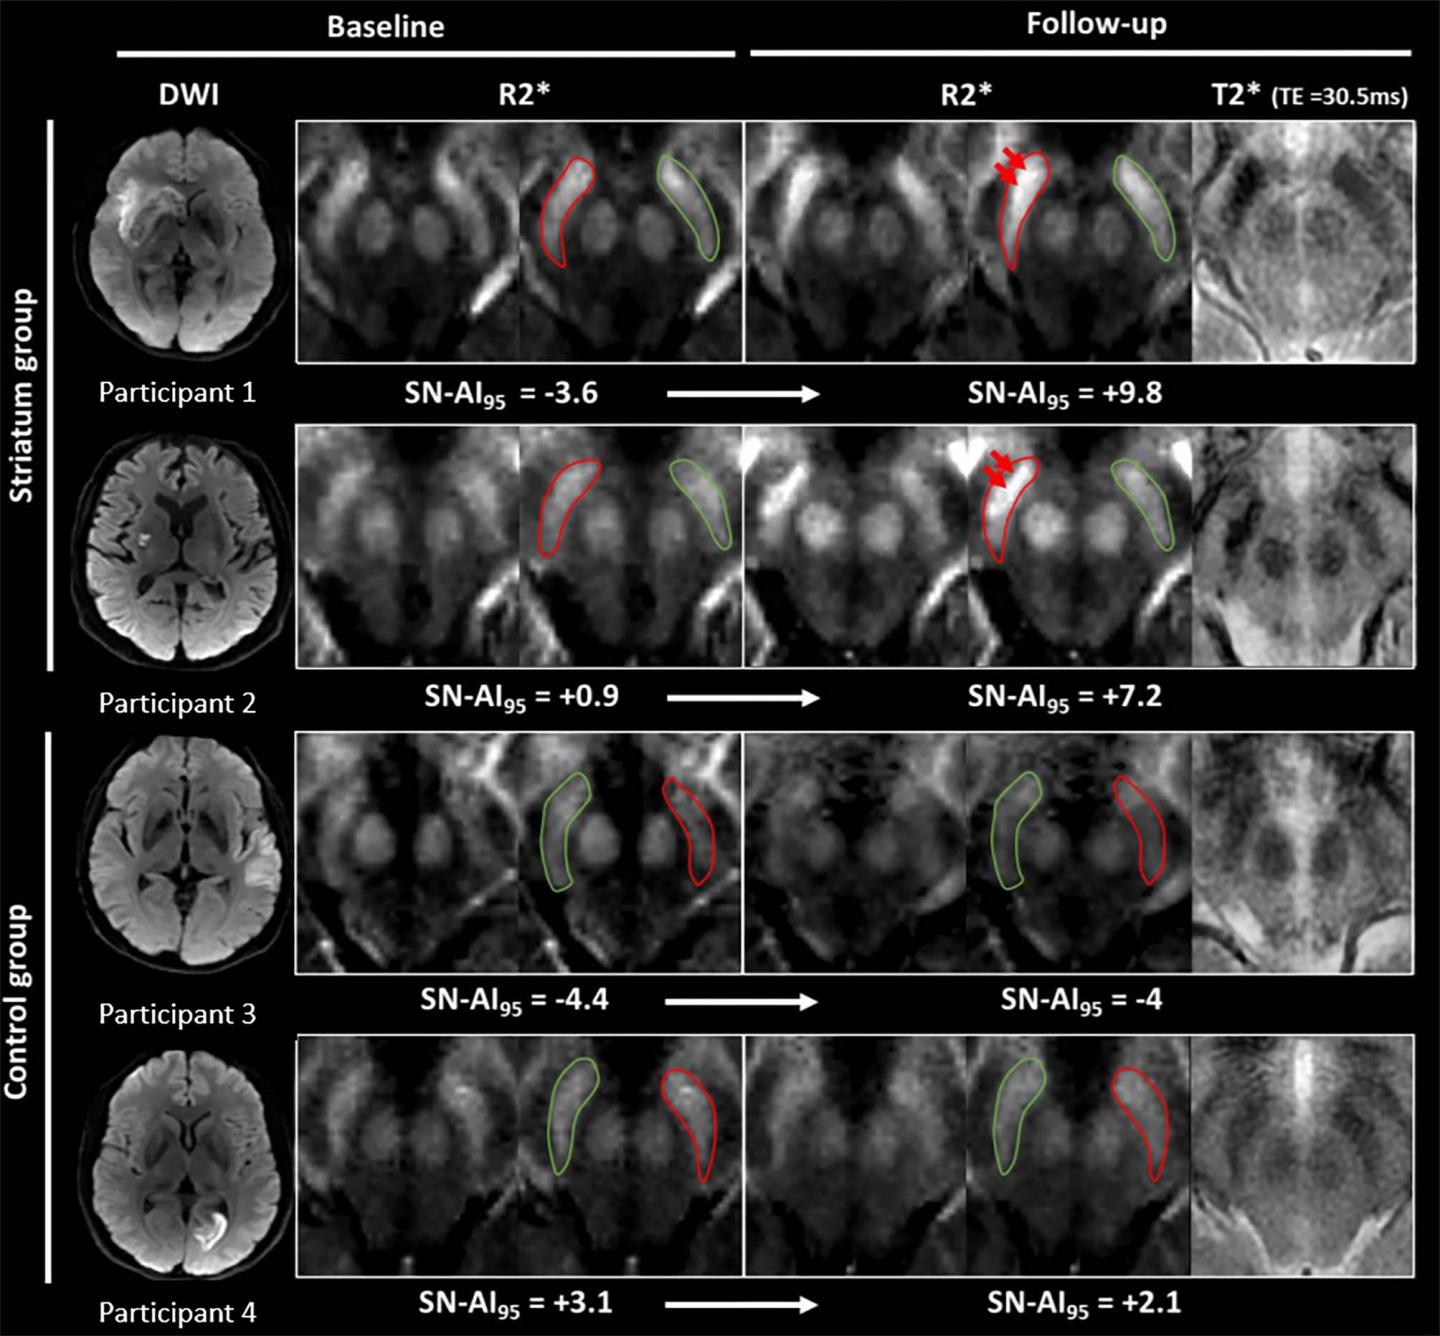

From www.eurekalert.org

Iron measurements with MRI reveal stroke's im EurekAlert! Iron Supplements Mri The iron is in the form of a superparamagnetic iron oxide that causes t1, t2, and t2* shortening on magnetic resonance imaging (mri). It is common mri knowledge that iron causes rapid mr signal dephasing and artifacts. To summarize our single‐center safety experience with the off‐label use of ferumoxytol for magnetic resonance imaging. Ferrous sulphate capsules contain approximately 65mg of. Iron Supplements Mri.